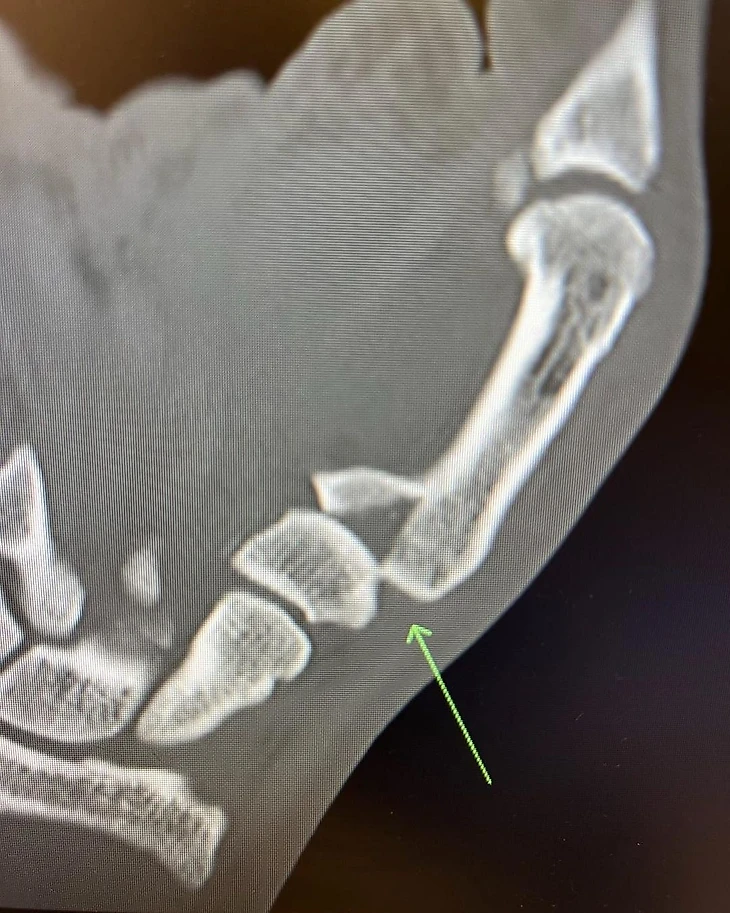

«Сломал большой палец во втором раунде, но это нас не останавливает! Сегодня у меня операция.

Я буду отсутствовать 12 недель. С нетерпением жду возвращения, спасибо всем за поддержку», – написал Волкановски в соцсетях, приложив фото рентгена.